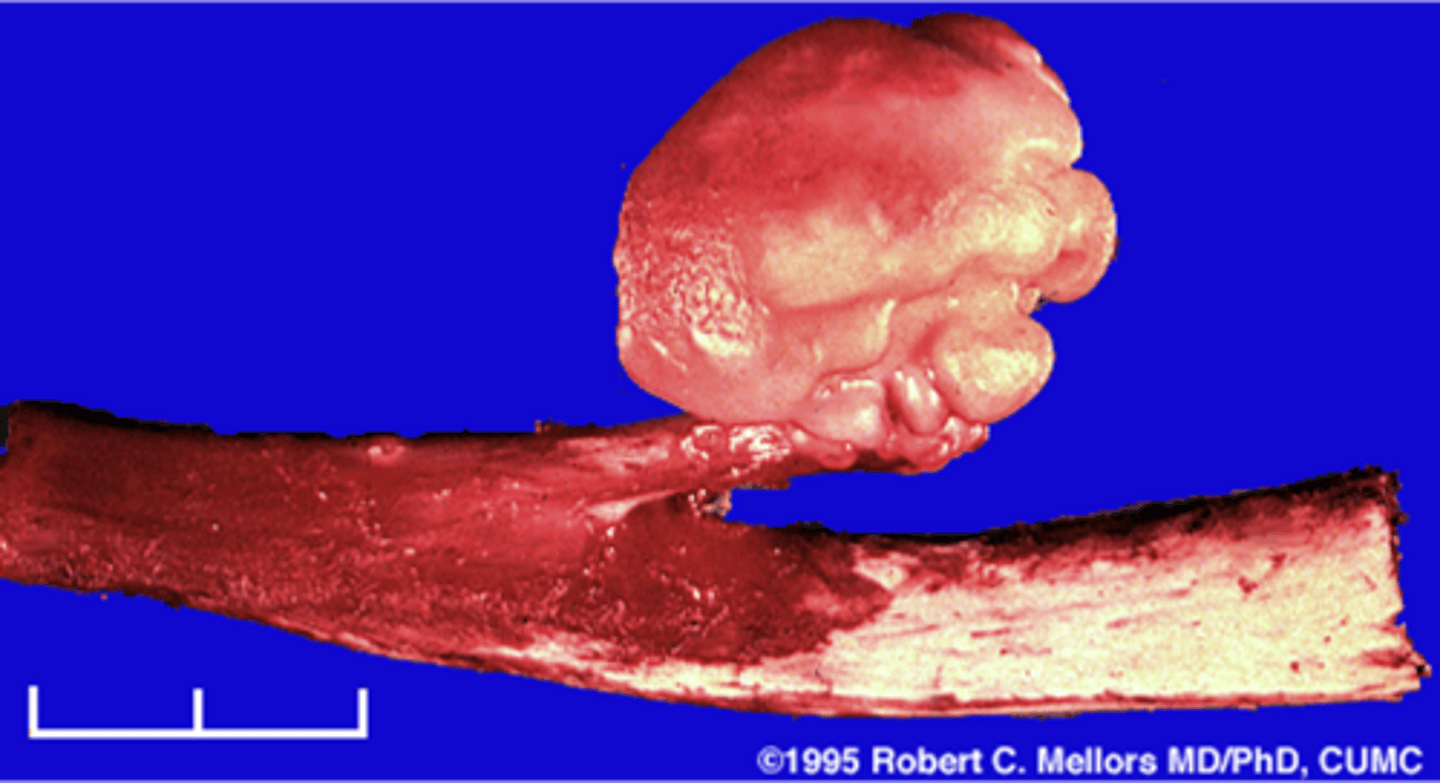

Pedunculated

_____ solitary osteochondroma:

- Metaphyseal

- Thin, elongated stalk

- Cortex and medulla continuous

- Calcified cap

- Projects away from joint

- Lucent when en face (on end)

<p>_____ solitary osteochondroma:</p><p>- Metaphyseal</p><p>- Thin, elongated stalk</p><p>- Cortex and medulla continuous</p><p>- Calcified cap</p><p>- Projects away from joint</p><p>- Lucent when en face (on end)</p>

Cartilage cap

What is this?

<p>What is this?</p>